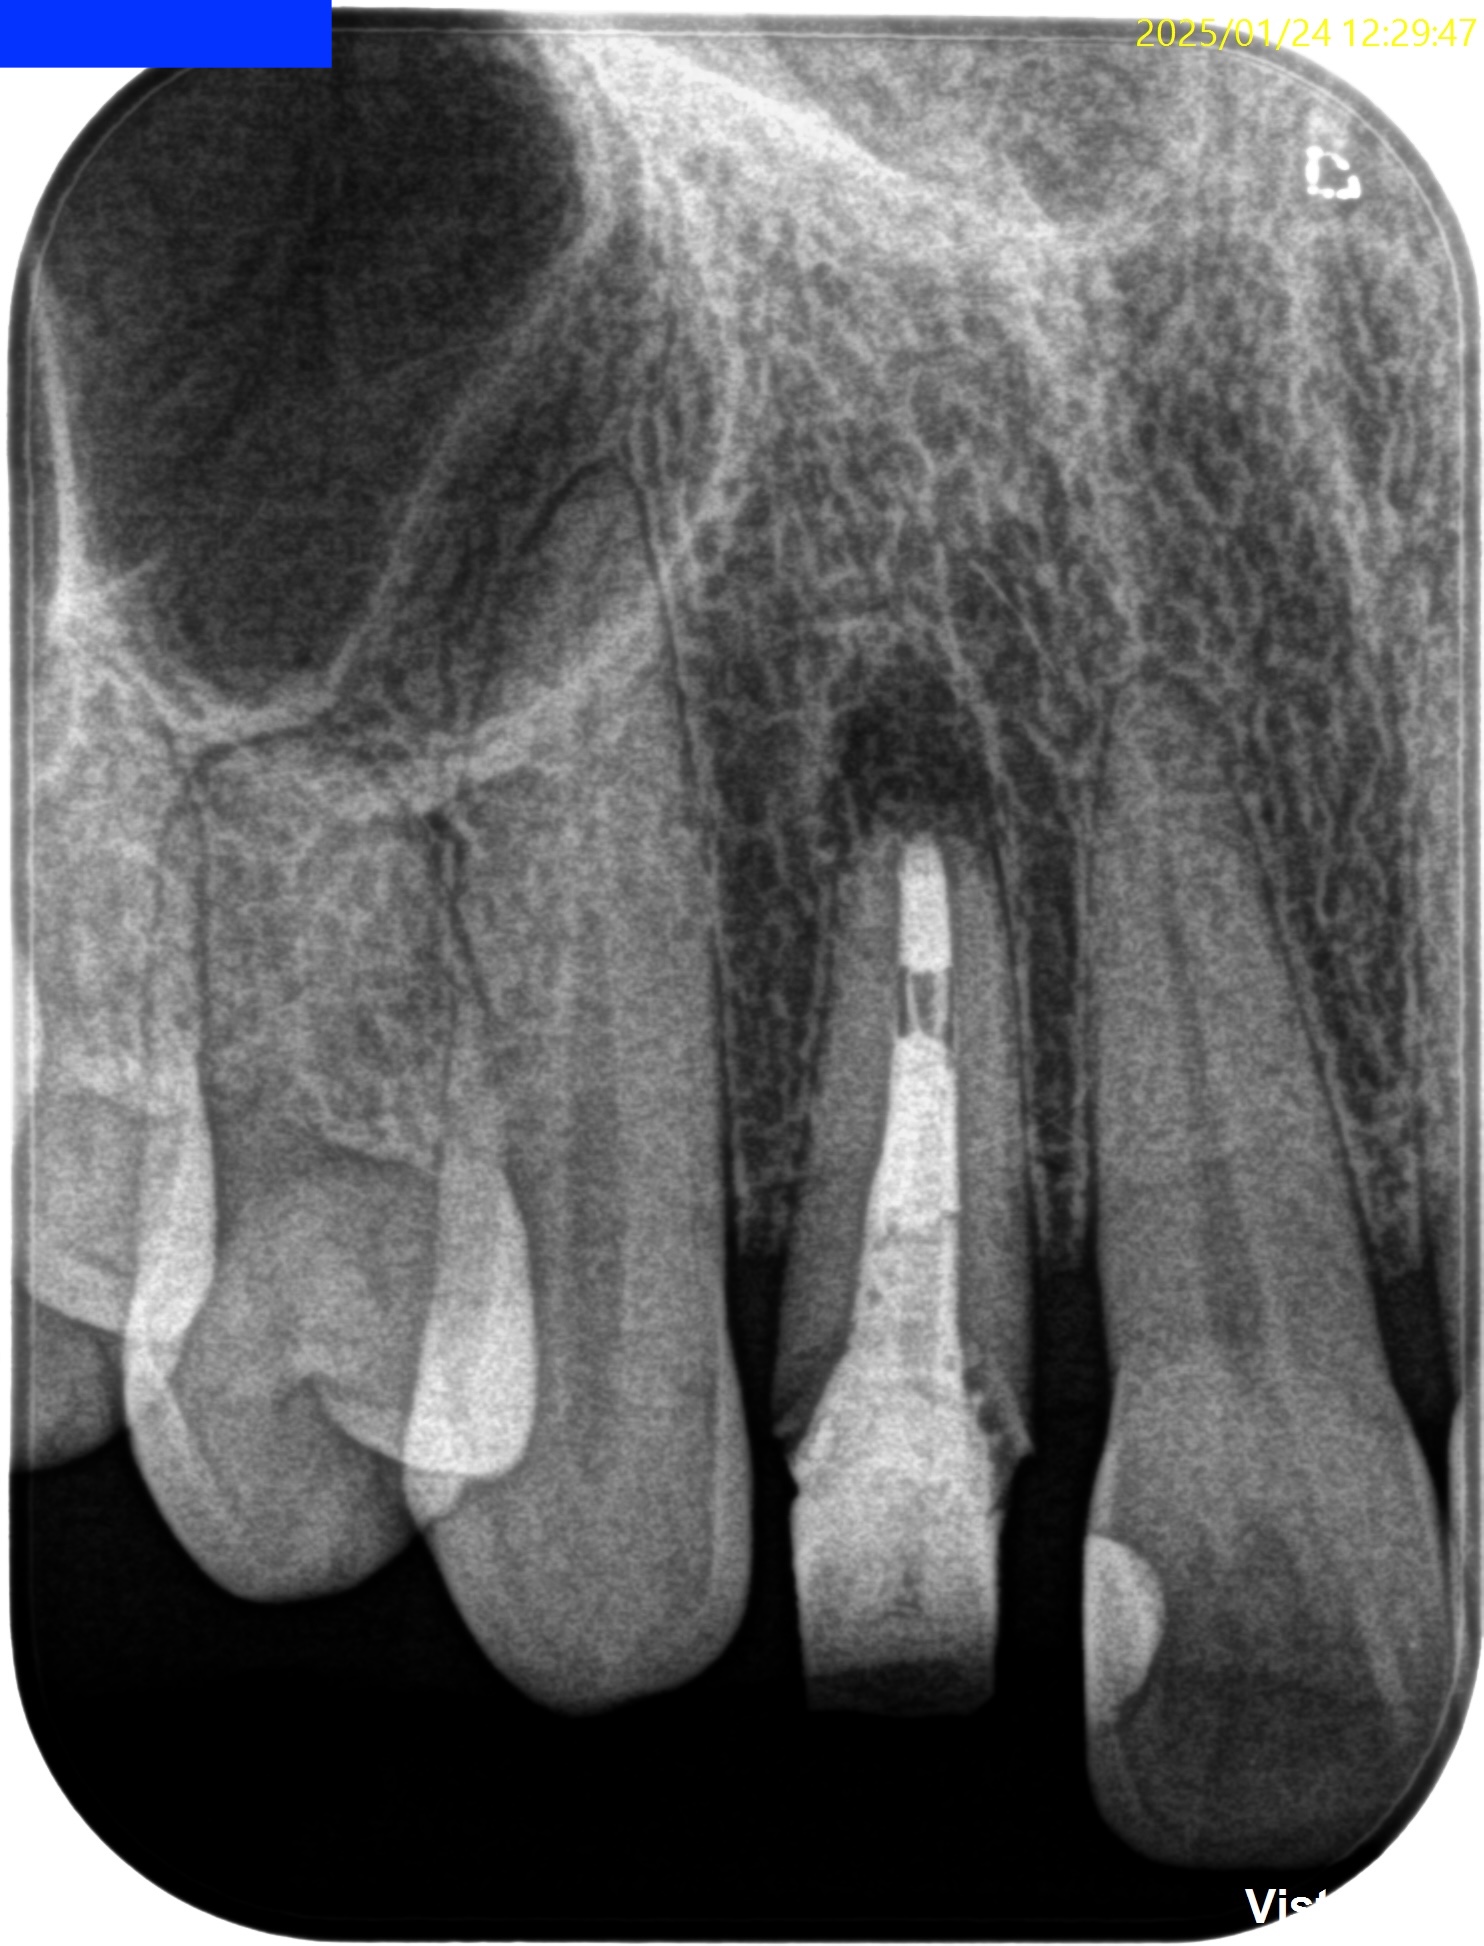

Pre-op Endo test(2025.1.24)

根尖が既に開いており、圧痛があったことから治療は再根管治療ではなく、歯根端切除術であるということがわかる。

クラウンのマージンより11.5mm下方に#7のApexはあり、そこを3mm切断するには頬舌的に4.4mmの幅があるということがわかる。

Pulp Dx: Previously treated

Periapical Dx: Asymptomatic apical periodontitis

Recommended Tx: Core build up w Fiber Post⇨Apicoectomy

術後にPA, CBCTを撮影した。